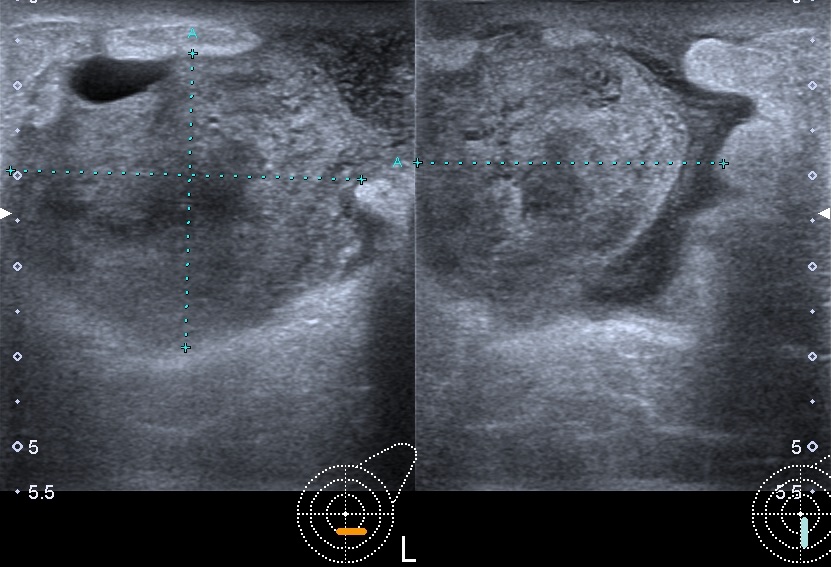

Our featured case is a young patient with a nipple piercing who developed a periareolar abscess. The four images below show the piercing, the abscess in two perpendicular planes, the drainage and the result after the drainage.

The video shows how the insertion of the needle can be performed under ultrasound guidance.